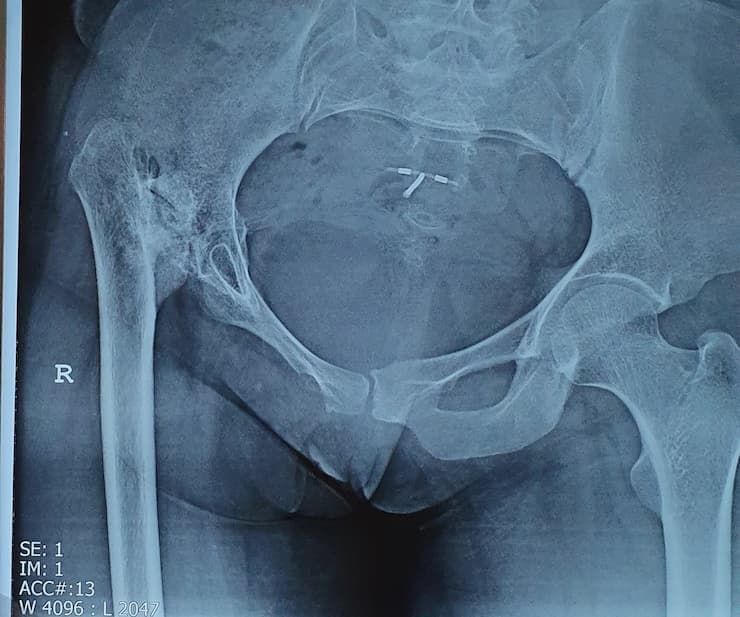

Дунд чөмөгний толгойн үхжил

Тодорхой шалтгааны улмаас дунд чөмөгний толгойд очих цусан хангамж алдагдаж, толгойн хэсэг тэжээлгүй болсноор дунд чөмөгний толгой нь үхжилт бүхий өөрчлөлтөнд ордог түгээмэл эмгэг юм.

Түнхний үе солих мэс засал гэж юу вэ image3

Мэс заслын өмнөх болон дараах рентген зураг